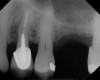

The implant is then delivered and should be well stabilized in the bone. If there is any mobility of the implant, it can either be placed a little deeper (if there is enough native bone) or the implant can be removed and the procedure aborted, in which case it would be a two-stage procedure. This should rarely occur with the tapered designed implant, even with only 2 mm of native bone. Using a bone-level platform-shifting implant (or a tissue-level designed implant) is critical, as the hard and soft tissue will establish a biologic width. If an external hex type of implant is used and the shoulder is placed at the bone level, an expected bone loss of 1.5 mm to 2 mm will occur.24 Figure 10 shows proper bone-level implant depth placement with a platform-shifting design. In this case, a 3-mm healing abutment was placed at the time of surgery to avoid a secondary uncovering surgery, but an implant-level healing abutment could have been placed instead. As can be seen, there was only about 2 mm to 3 mm of native bone height. The membrane was raised about 8 mm to 9 mm. Comparing the radiograph on the day of surgery (Figure 10) to the 6-month postoperative radiograph (Figure 11) shows no loss of native bone, as well as the positive change in appearance of the grafted bone. The 3.5-month CBCT scan (Figure 12) shows good healing of the bone with no coronal bone loss. With minimal native bone present, as in this case, the use of a non-platform-shifting or non-tissue-level implant design could be problematic. After 1.5 mm to 2 mm of crestal bone loss, an external hex designed implant could develop instability with possible implant failure. If a non-tapered implant is used and bone loss occurs during healing, migration of the implant into the sinus could potentially occur. The surgeon can use either a healing abutment or implant-level closure screw over the implant shoulder. With patients who tend to use their tongues to explore or play with the area, or if the area is under a removable partial denture, a closure screw is recommended.

A 74-year-old man presented with only about 2 mm to 3 mm of native bone below the sinus in the No. 14 position (Figure 13). The composite graft used was an approximately 50:50 mixture of DFDBA (Bio-Oss®, Geistlich Biomaterials, www.bio-oss.com) with the addition of about 40% calcium sulfate by volume (Figure 14). The implant placed (Figure 15) was a 10-mm long, rough-surfaced, platform-shifting implant (tapered 4.2 mm to 2.8 mm), and the sinus was raised about 8 mm. The postoperative radiograph taken at 4 months (Figure 16) showed some shrinkage of the graft, but no demarcation of the old sinus floor in the area.